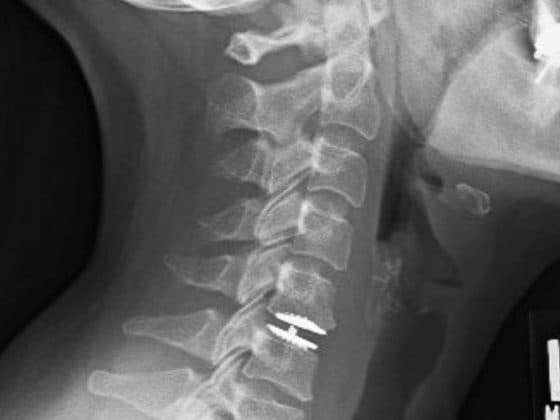

Cervical Disc Replacement

Cervical disc replacement is a surgical procedure for the neck that replaces a damaged spinal disc with an artificial one. This surgery is a modern alternative to spinal fusion for treating degenerative disc disease, a herniated disc, or other conditions causing chronic neck pain or arm pain, numbness, or weakness. It can offer quicker recovery, less post-operative limitations and retain some of the motion of the spine when compared to a fusion procedure.

The surgeon makes a small incision in the front of the neck. The damaged disc is removed, and an artificial disc, typically made of metal and plastic, is inserted into the empty space between the vertebrae. Unlike fusion surgery, which locks the vertebrae together, the artificial disc is designed to mimic the natural motion of the spine. This can potentially reduce stress on the adjacent discs, lowering the risk of future problems.